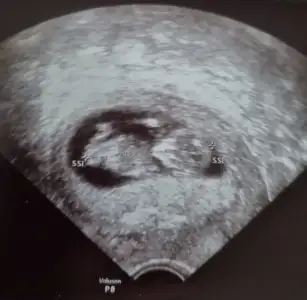

Net değil ama kız sanki başka USG varsa paylaşın 11 12 13 haftalar olmalıTahminlerinizi alabilirmiyim??? 12. Haftadan resim

Net değil ama kız sanki başka USG varsa paylaşın 11 12 13 haftalar olmalı

Yukari dogru cikanlar bacaklari degilmiNet değil ama kız sanki başka USG varsa paylaşın 11 12 13 haftalar olmalı

Ben size yazmıştım kız dedim diğer konudaBana ısrarla bakmadınız 12 hafta karından![]()